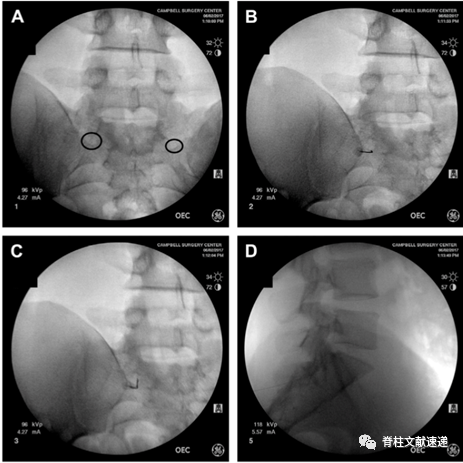

2.1.  俯卧位,常规消毒,定位,正位时调整C臂机,与L5/S1椎间隙平行,黑圈所示为骶1孔,后孔易与较大的前孔混淆(上图A)

2.2.  先将穿刺针扎中骶1孔远端的骶骨(上图B),再逐渐滑行调整至骶孔(上图C)。

2.3.  侧位透视,针尖不应该位于骶管腹侧,理想的位置是紧贴S1椎弓根尾下缘,位于椎板下约5mm(上图D)。

2.4.  穿刺位置良好后,抽吸测试,若无血液和脑脊液,可行造影剂观察(上图E、),再行局麻药物注入。